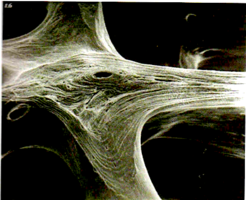

2. Поверхность и структура материала для изготовления биоимплантатов